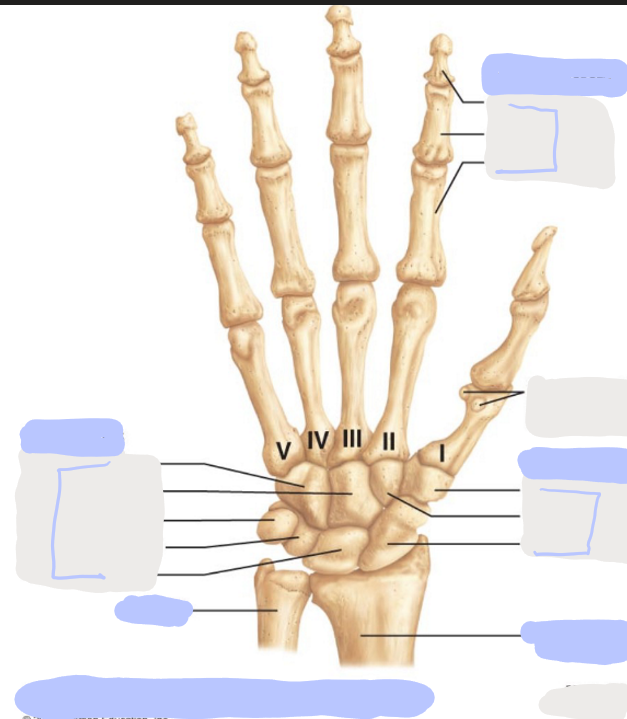

What is this picture of?

Posterior View of the Right Hand

What is here?

Where is the Ulna?

What is here?

Where is the Radius?

What is here?

Where are the Metacarpals?

What is here?

Where are some of the Carpals?

What is here?

Where are some of the Carpals?

How many carpals are there?

8

How many metacarpals are there?

5

How many phalanges are there?

14